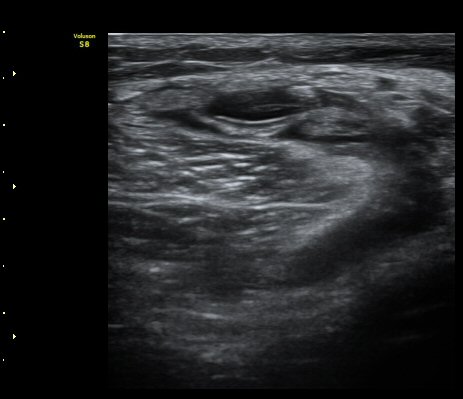

ÈíÀÎ ÈÄ ¹«¸ µÚ ¿À±Ý Ⱦ´Ü¸é°Ë»ç¿¡¼ ³»Ãøºñº¹±Ù°ú ¹Ý¸·¾ç±Ù »çÀÌ¿¡ Àú¿¡ÄÚ ¼ö¾×Àú·ùÀÇ °¨¼Ò°¡ °üÂûµÈ´Ù(»çÁø 3).